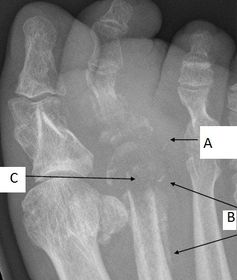

What disease is this? What is shown by A, B and C? | Psoriatic arthritis. A = destructive changes B = Pencil in cup deformity C = IPJ fusion |